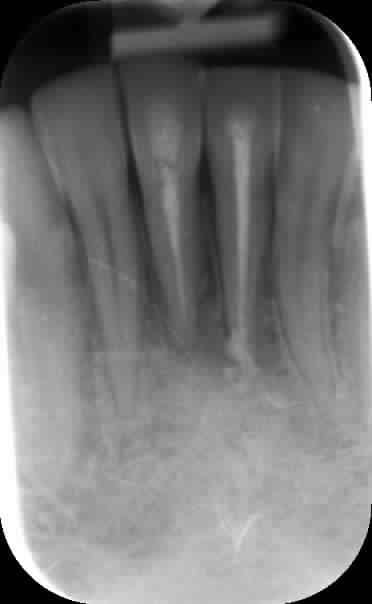

Quand même, un petit cas sympa endo-paro avec mobilités et fistule. Aujourd'hui, tout va bien : plus aucune sensibilité ni mobilité.

20/03/13, 24/04/13, 04/06/14